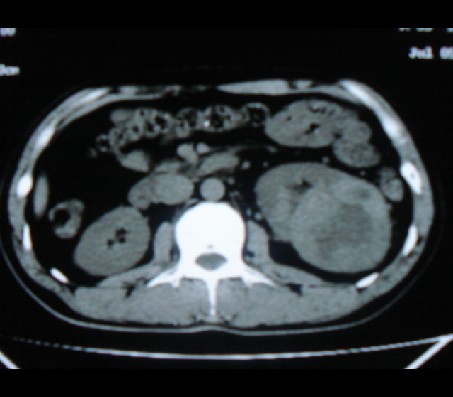

左肾癌侵犯肾盂可能性大,建议增强.

考虑左肾癌可能性大,建议增强扫描。

左肾癌侵犯肾盂可能性大。

肾癌侵犯肾盂,肾盂出血,肾盂内为血肿

首先考虑恶性肿瘤性病变,考虑左肾癌可能性大,建议增强扫描。